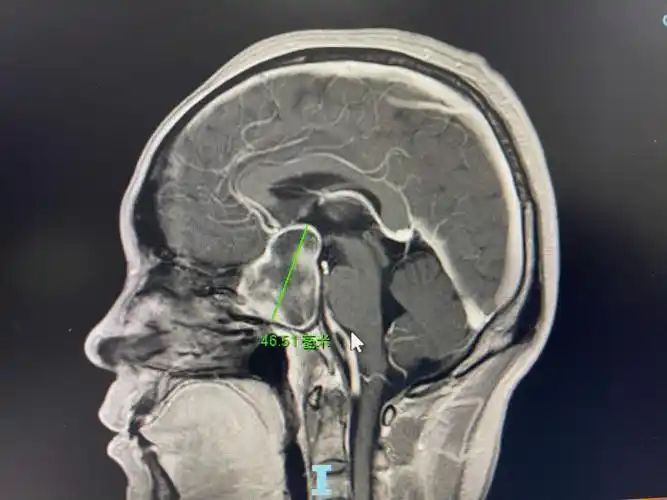

头痛视力下降警惕垂体瘤伴出血

脑垂体的位置:位于颅底蝶骨体上面的垂体窝内,上端与下丘脑相连.

蝶鞍区 (1)垂体与垂体窝 hypophysis 位置 垂体窝 垂体